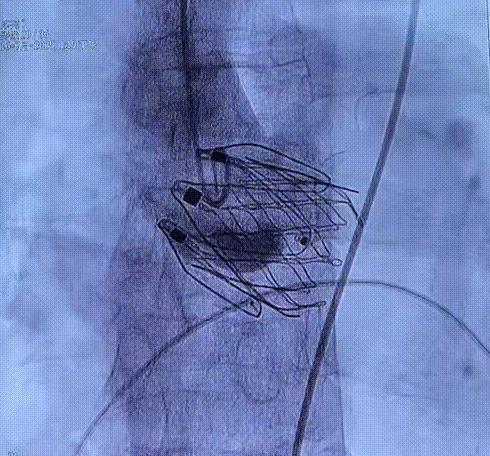

术中回顾及效果

在DSA与超声引导下,手术团队高效精准地完成了瓣膜的定位、释放与功能评估。手术过程顺利,夹持件入窦与定位一气呵成,三枚夹持件的释放与锚定位置与术前评估完全一致,器械用时仅6min左右。患者主动脉瓣重度反流纠正,术后无反流、无瓣周漏。术后心脏彩超显示人工生物瓣启闭良好,平均跨瓣压差3mmHg,流速正常,舒张压从30mmHg提升至70mmHg。

夹持件顺利入窦

夹持件入窦后撤内鞘

瓣膜释放

术后造影